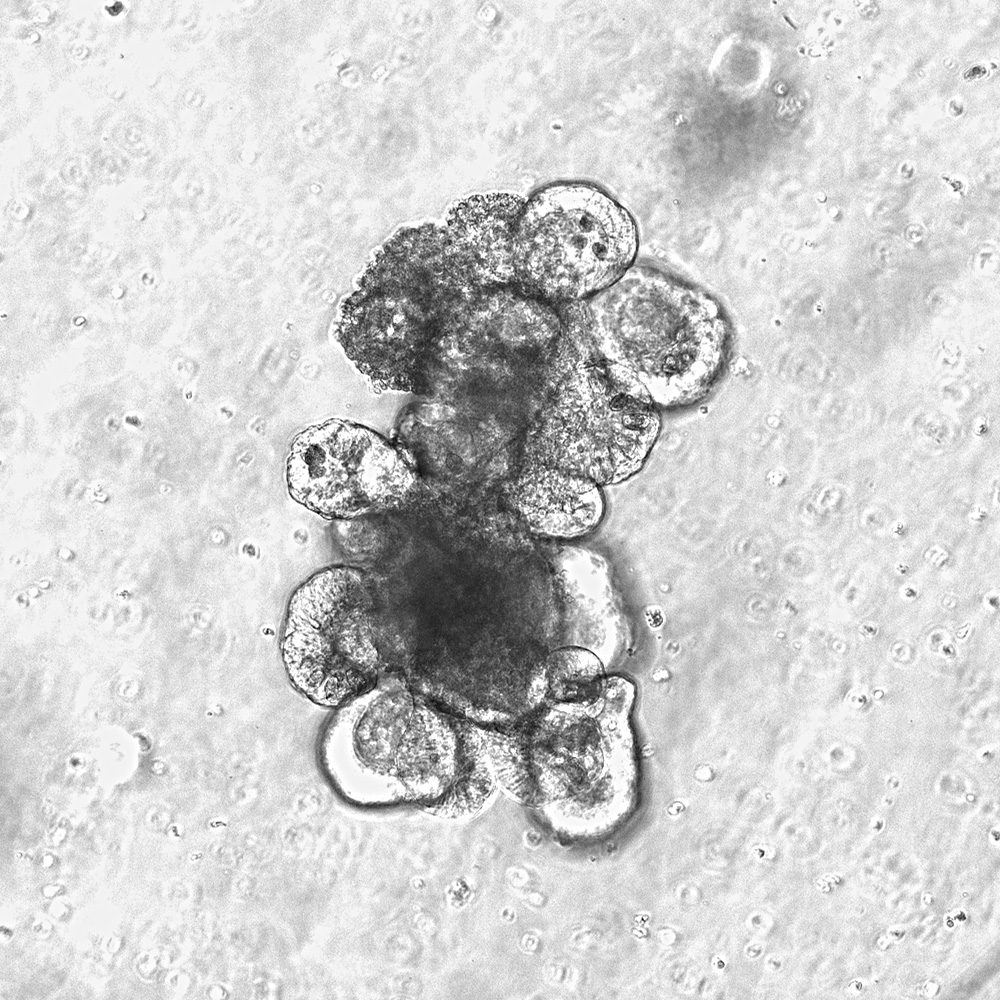

Small “mini intestines”: modern organoid cultures used to analyze the effects

The researchers examined tissue samples from patients who had undergone stem cell transplantation, as well as various mouse models for radiation- and therapy-induced intestinal damage. In addition, modern organoid cultures - small “mini-intestines” made from human stem cells in the laboratory were used to specifically analyze the effects of the bacterial metabolite on the intestinal lining.